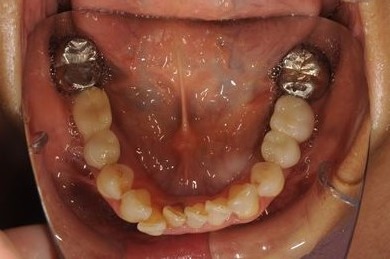

インプラントの症例写真 IMPLANT

骨再生インプラント治療

| 性別/年齢 | 女性 / 51歳 | ||||||||||||||||||||||||||||||||

| 主訴 | 他の歯科医院で入れ歯を入れたが、滑舌や味などで不自由を感じている。インプラントは難しいと言われたが、可能かどうかみていただきたい。 | ||||||||||||||||||||||||||||||||

| 治療方針 | サイナスリフトにより上顎洞を拳上し、インプラント治療を可能にする。 | ||||||||||||||||||||||||||||||||

| 治療内容 | インプラント3本(サイナスリフト)、ハイブリッドセラミッククラウン5本 | ||||||||||||||||||||||||||||||||

| 総治療費 | 2,111,813円 | ||||||||||||||||||||||||||||||||

| 治療期間 | 1年3ヶ月 |